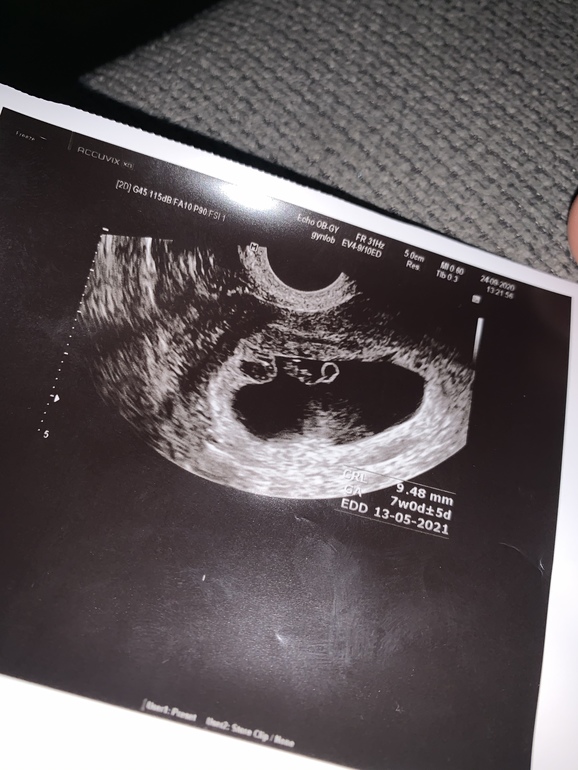

Сегодня была на узи (7 недель 3 дня), по узи 7 недель и 5 дней. КТР 9.5 мм

Единственное что меня беспокоит, это само узи... мне кажется что эмбрион сильно маленький по сравнению с мешочком, плюс мне кажется что есть гематома (по левую сторону от эмбриона, были кровянистые выделения две недели назад), да и не понятно что за помехи в самом мешочке... какой-то он не ровный и не четкий...

Я имею ввиду что сам мешочек в котором он находится мне кажется что он сильно большого размера для 7 недель

Вы имеете ввиду плодное яйцо? А какие размеры у него вам написали? У меня пя тоже по сроку опережает эмбрион, врач говорит это нормально, бывает 🤷 Главное, чтобы ктр соответствовал сроку.